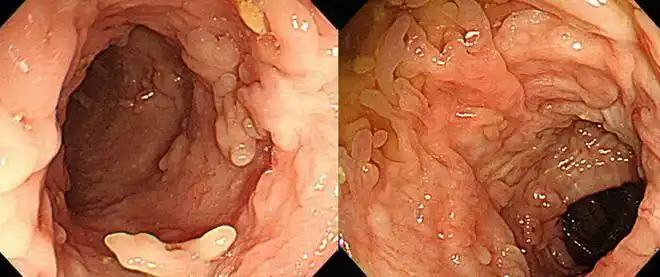

炎症|腺瘤|直肠_网易订阅